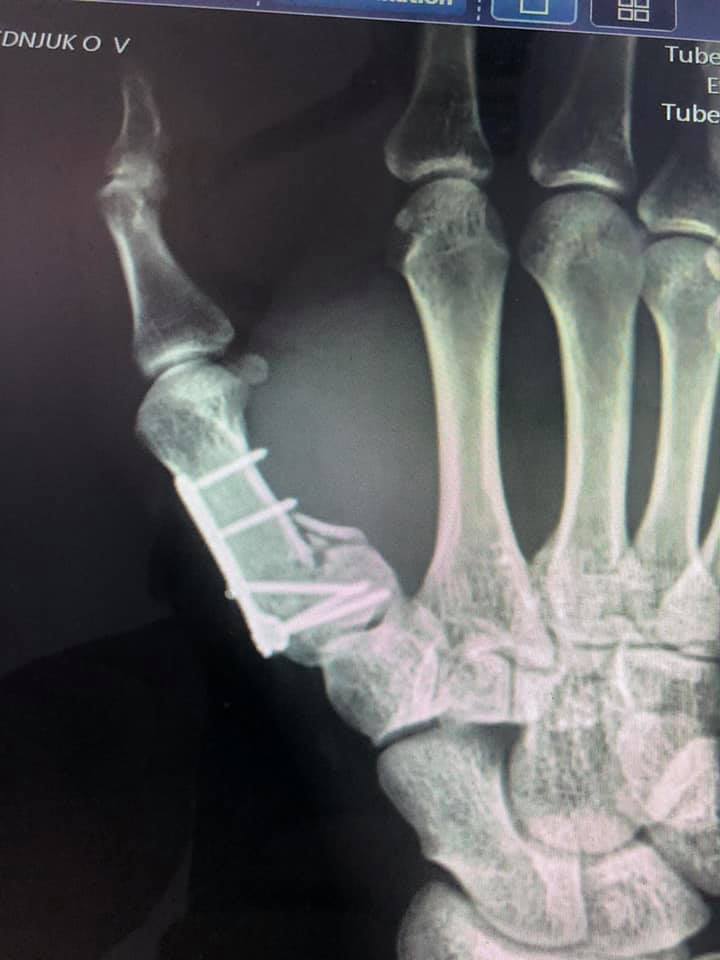

Пацієнт з висоти росту впав на землю. В ургентному порядку був оглянутий в КНП «НЦМЛ». Після огляду лікарем був встановлений діагноз: закритий перелом І п’ясної кістки правої кисті.

Волинянину провели оперативне лікування: остеосинтез п’ясної кістки та фіксація титановою міні-пластиною.

Операція проведена успішно.